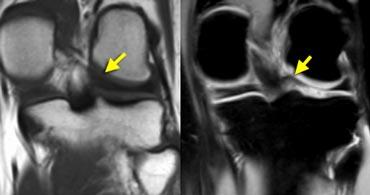

TRÁI: chân bám sụn chêm trong bình thường nằm ngay phía trước dây chằng chéo sau. PHẢI: mất chân bám sừng sau do rách chân bám sụn chêm.

Chân bám sừng sau nằm ngay phía trước dây chằng chéo sau.

Nếu không thấy chân bám này trên các lát cắt sagittal, cần nghĩ đến rách chân bám sụn chêm (hình minh họa).